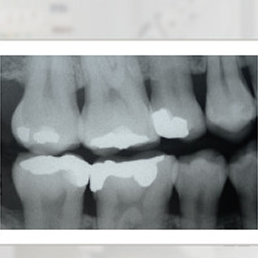

X-ray examination showing the crowns of both lower and upper teeth in the wing area. It allows for diagnosing caries in this area and assessing the tooth contact surfaces. It is used in conservative dentistry and dental prosthetics.

- Bitewing X-ray – especially useful in diagnosing interproximal caries, contact surfaces, and assessing bone levels around the teeth. It allows simultaneous imaging of the crowns of upper and lower molars and premolars, which is why it is often used in conservative and prosthetic dentistry.